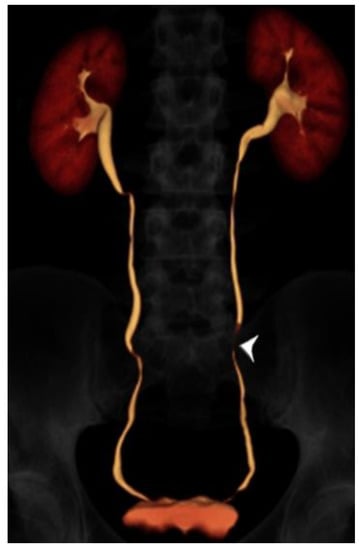

2.2. CT Urography Technique

- Noorbakhsh, A.; Aganovic, L.; Vahdat, N.; Fazeli, S.; Chung, R.; Cassidy, F. What a difference a delay makes! CT urogram: A pictorial essay. Abdom. Radiol. 2019, 44, 3919–3934. [Google Scholar] [CrossRef]

- Cheng, K.; Cassidy, F.; Aganovic, L.; Taddonio, M.; Vahdat, N. CT urography: How to optimize the technique. Abdom. Radiol. 2019, 44, 3786–3799. [Google Scholar] [CrossRef]